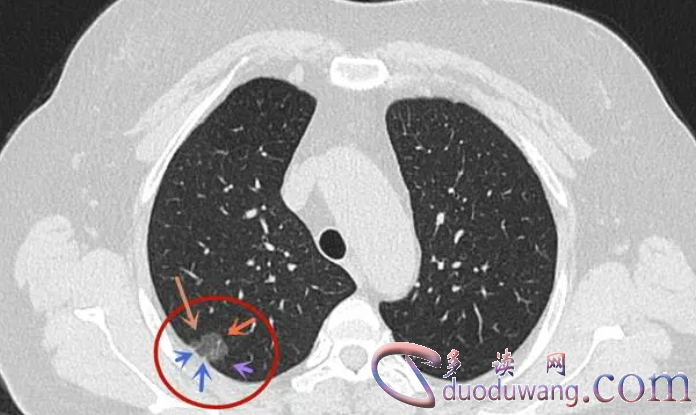

肺部磨玻璃结节是指肺部CT影像上呈现为部分透亮的斑点,类似于磨砂玻璃的外观。它通常是由肺泡间质增生、炎症渗出或血管扩张等引起的肺泡实变所致。

肺部磨玻璃结节的出现可能代表了多种慢性疾病或病理情况,包括感染性疾病、肺泡蛋白沉积症、非典型肺炎、肺部转移瘤等。因此,一旦发现肺部磨玻璃结节,需要进一步的检查和诊断,以明确病因并采取相应的治疗措施。

肺部磨玻璃结节还需要与其他肺部病变进行鉴别诊断,如肺囊胞、肺部占位性病变、肺脓肿等。这需要综合考虑临床症状、影像学特征和实验室检查结果,进一步明确诊断。